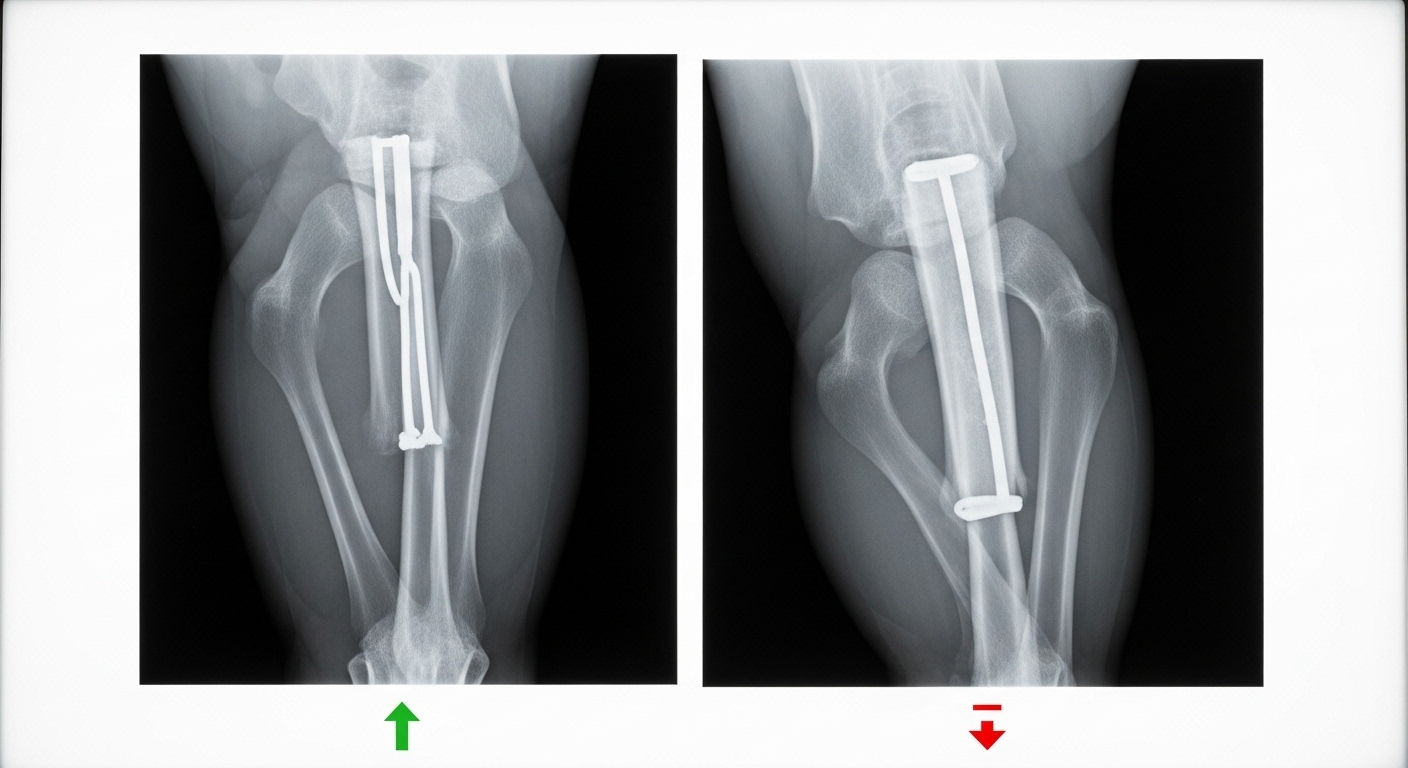

La théorie est séduisante, mais qu’en est-il en pratique ? L’équipe a testé son dispositif sur des lapins de Nouvelle-Zélande présentant des fractures sévères du fémur. Certains ont reçu l’implant bio-imprimé, les autres un ciment osseux classique. Douze semaines plus tard, le verdict était sans appel : les lapins du premier groupe montraient une guérison osseuse bien meilleure, avec une densité et une surface osseuse supérieures. Et surtout, aucune trace d’infection ou de nécrose n’a été observée.

vers une application en clinique ?

Le chemin vers les blocs opératoires humains est encore long. Il faudra encore valider la technique sur de plus grands animaux et mettre en place des protocoles de fabrication et de stérilisation irréprochables. Mais si ces étapes sont franchies, on pourrait bien assister à une petite révolution, transformant la réparation osseuse en un acte plus rapide, plus sûr et véritablement sur mesure, réalisé en direct sous les yeux du chirurgien.